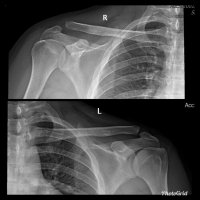

AC JOINT SEPARATION

AC joint separation, often called a shoulder separation, is a dislocation of the clavicle from the acromion, with disruption of the acromioclavicular ligaments and/or coracoclavicular (CC) ligaments.

- Normal AC joint distance <5mm. Variation exists but with clinical suspicion any measurement >8mm is concerning for injury, comparison to normal contralateral side also useful.

- Normal CC joint distance 10-13mm. Displacement measured from superior border of the coracoid process to the inferior border of the clavicle.